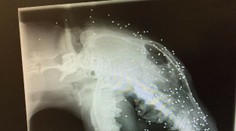

Životné prostredie Potápači, ktori skúmali vrak lode, narazili na veľkú raritu. Ako presne vzniká, je záhada Karol Chren 14. 10. 2019